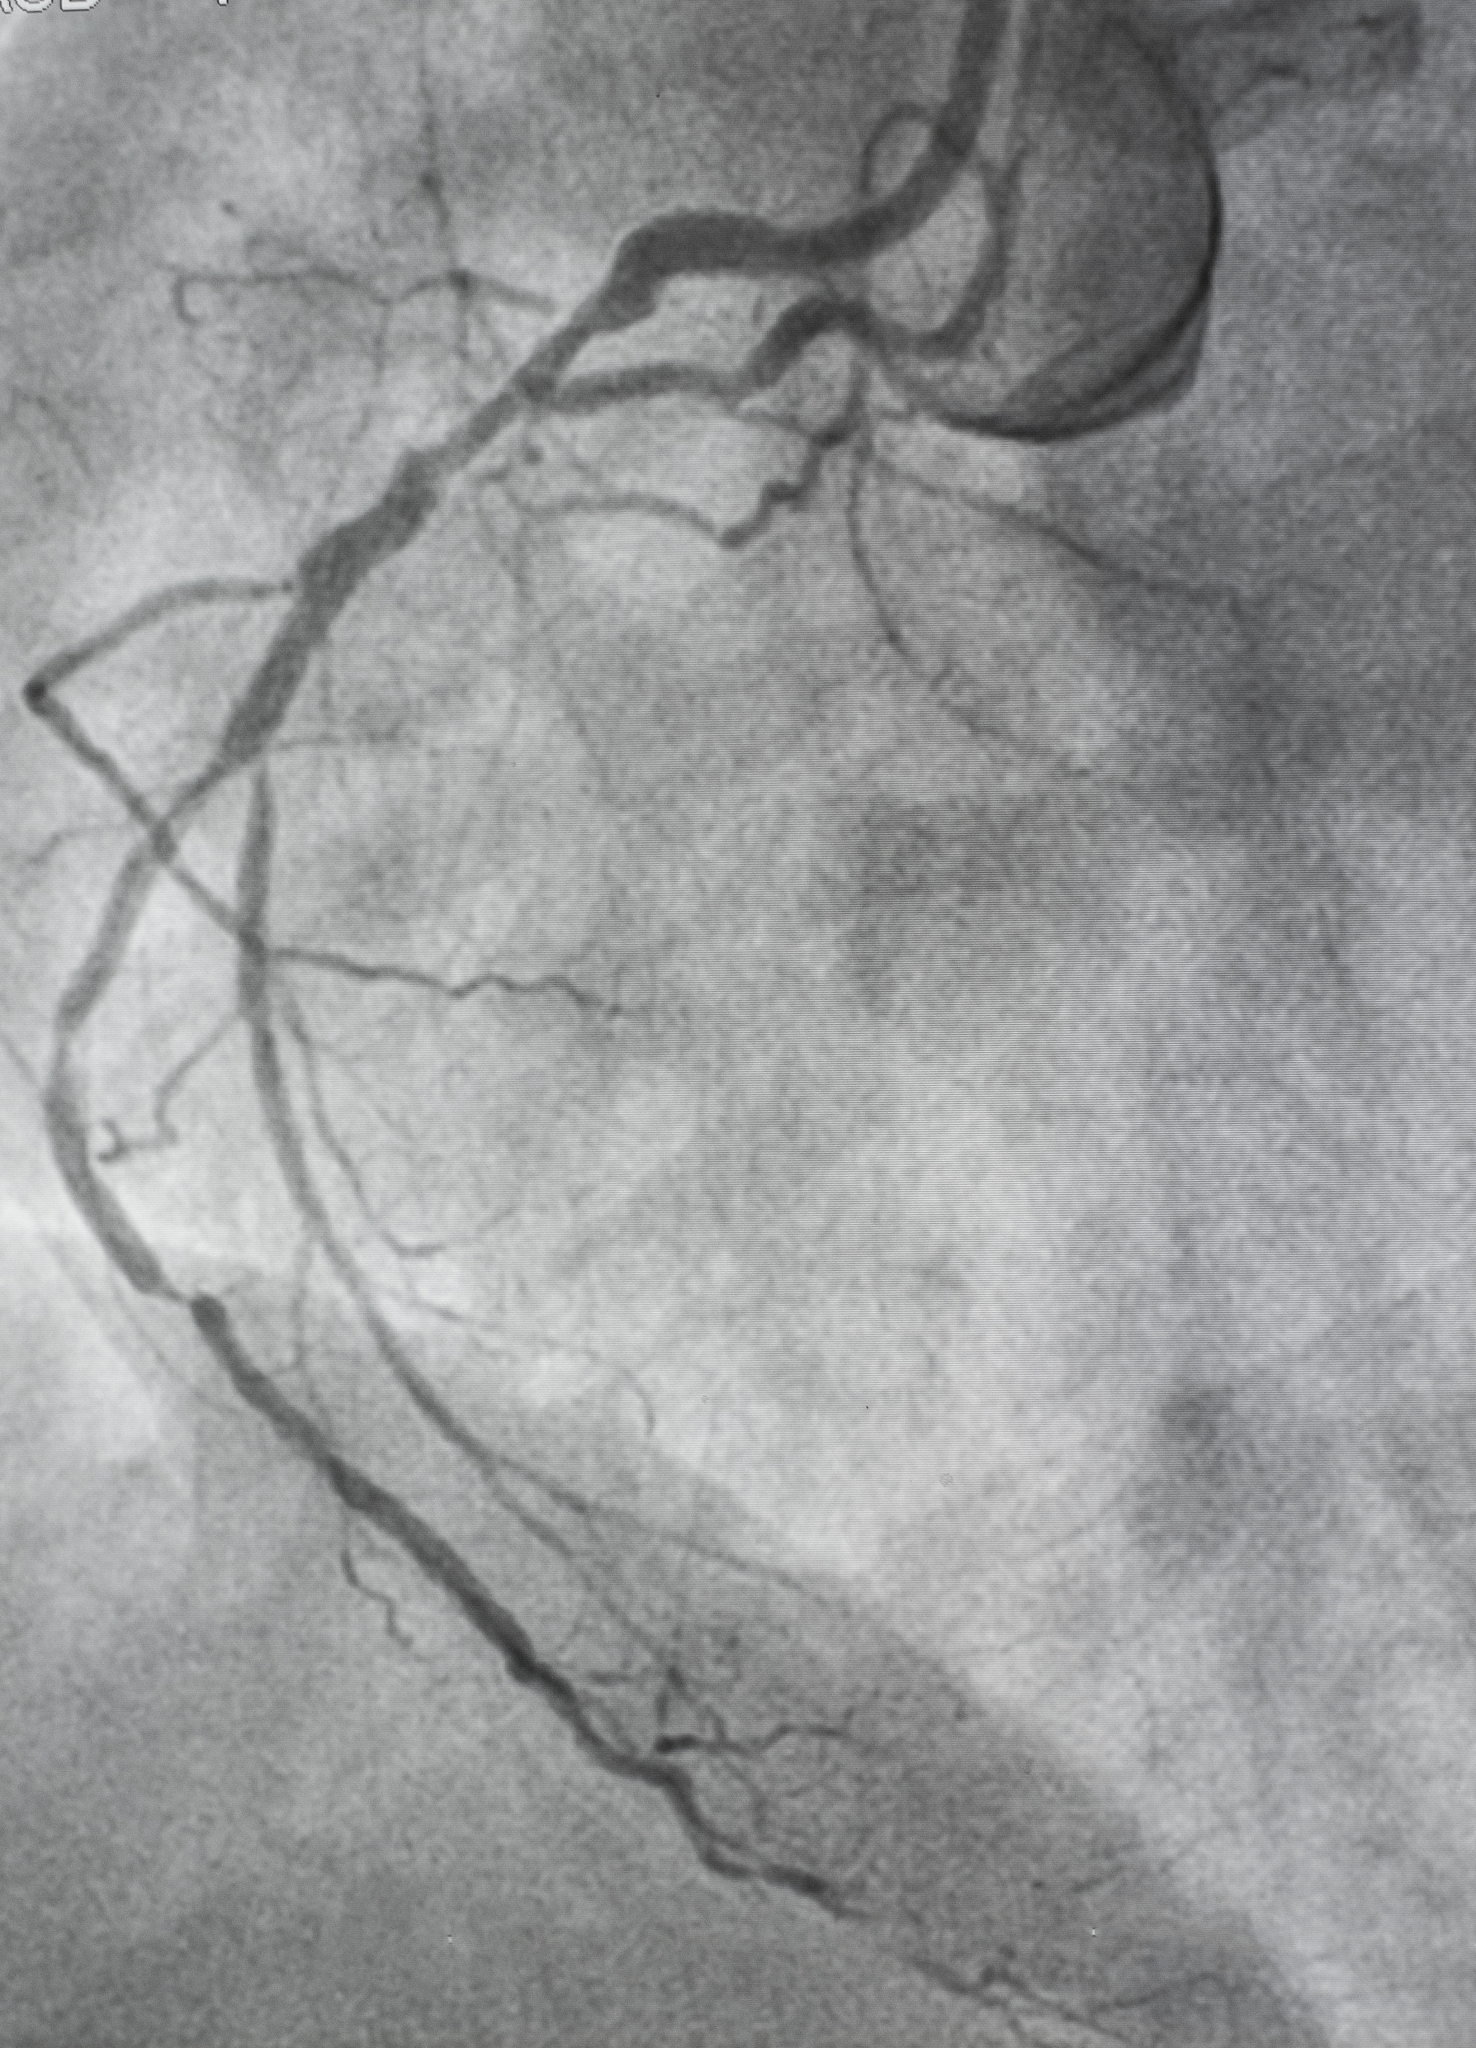

冠脉介入术是一种通过导管在心脏血管内进行的治疗性手术,用于治疗冠心病、心肌梗死等心血管疾病。在导管室内实施冠脉介入术已成为现代医学中的常规治疗方法。

目前,冠脉介入术在导管室内实施已经非常成熟。导管室内设备和技术已经得到了极大的发展,能够满足各种不同的患者病情和手术需求。导管室内设备包括血管造影机、导管、支架等,技术包括介入医师的操作技巧和团队协作等。

冠脉介入术在导管室内实施的优点是手术时间短、创伤小、恢复快、治疗效果好等。同时,导管室内设备和技术的不断更新也为冠脉介入术的实施提供了更好的保障。

总之,冠脉介入术在导管室内实施已经成为现代心血管医学中的重要治疗手段,对于患者的治疗效果和生活质量提高起到了积极的作用。